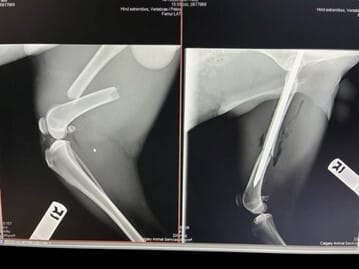

One-and-a-half-year-old border collie cross Wally recently received major femur surgery. When he arrived at the Animal Services Centre as a stray in mid-October, Wally was fearful, and it was apparent he needed medical attention—not only was he emaciated, but he also had a fractured femur.

Wally’s X-rays